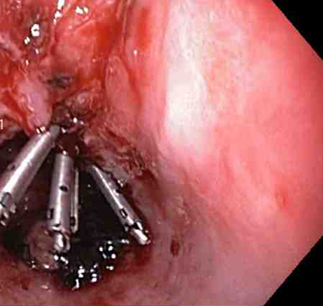

Three haemoclips deployed to complete closure of the mucosal defect

From the collection of Juan Carlos Munoz, MD, University of Florida